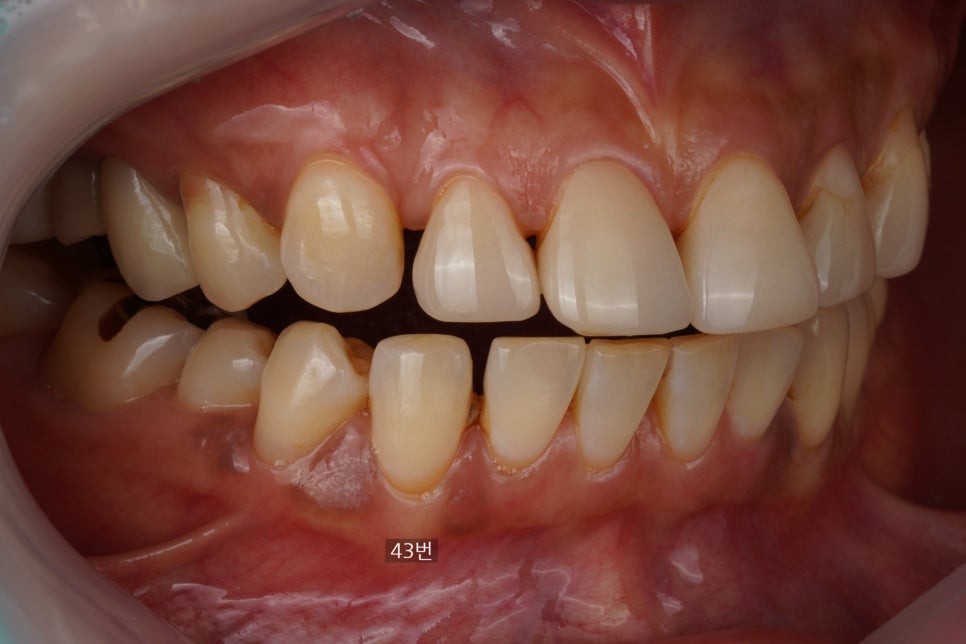

사진상 왼쪽 송곳니 부위

위 사진에서 왼쪽 송곳니 부위(43번치아)에

기존에 치료했던 레진이 떨어지셨다고

말씀을 해주셔서 사진을 찍고

분석을 해보았습니다.

옛날 레진 (마모와 변색, 치석침착이 보입니다)

왜냐면 사진에서 보시다시피

옛날 레진이 다 마모가 되어있고

그 주변으로 변색도 있고

레진 하방으로 치석도 많이 쌓여 있어서